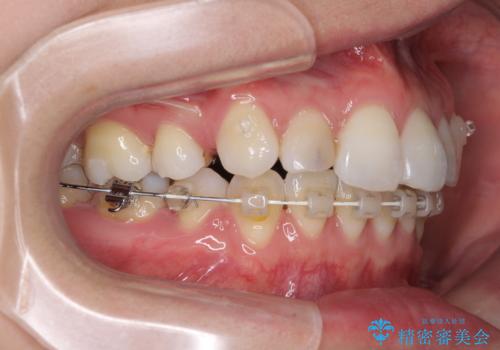

- ハーフリンガル

目立たない装置を希望されたので、上顎が裏側装置のハーフリンガルを選択し、上下左右の小臼歯(計4歯)を抜歯して矯正治療を行うこととしました。

治療期間の目安は3年~3年半でしたが、咬み合わせにより上顎のスペースがなかかな閉じきらず、治療期間が長期化してしまいました。